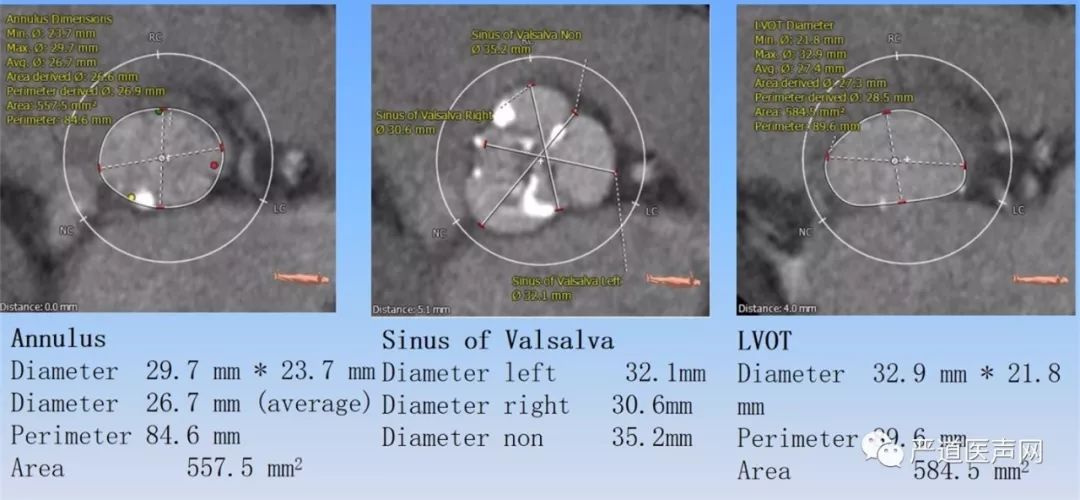

TAVR CTA分析结果

主动脉瓣瓣环直径 29.7*23.7 mm,瓣环周长84.6mm,面积557.5mm2,主动脉窦部直径32.1mm*30.6mm*35.2mm,左心室流出道周长89.6mm,面积584.5mm2。(如下图)

左侧冠脉开口高度较低9.0mm,右侧冠脉开口14.5mm。(如下图)